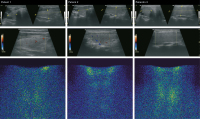

Der Schilddrüsenfall: Amiodaron-induzierte Thyreoiditis Typ 2 – Langzeitverlauf einer Fallserie aus dem Jahr 2010

Journal für Klinische Endokrinologie und Stoffwechsel - Austrian Journal of Clinical Endocrinology and Metabolism 2017; 10 (1): 12-14 Volltext (PDF) Abbildungen